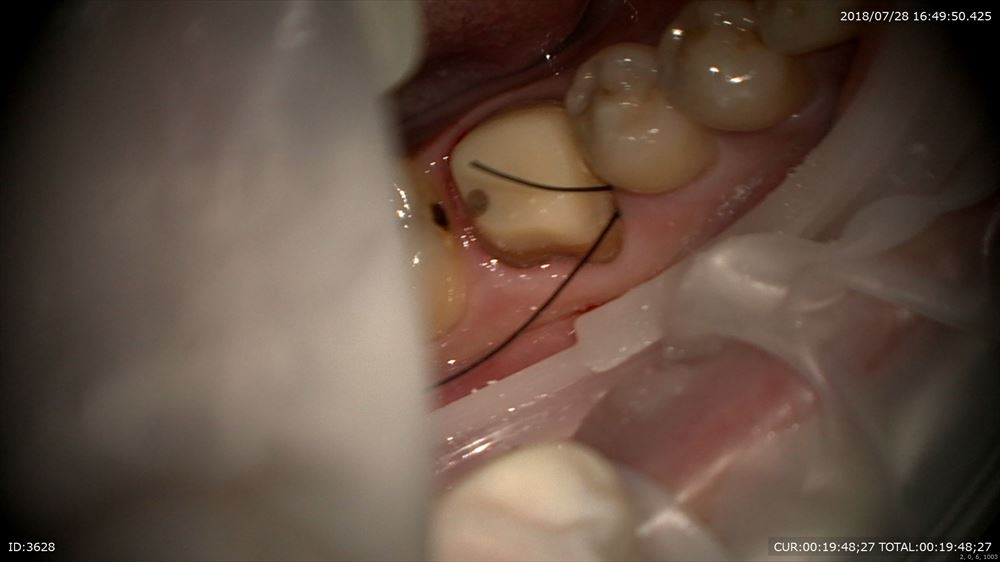

この様に仮歯で2ヶ月観察。問題なし。歯周病学会認定衛生士の歯周治療後私に昨日帰ってきました。

再発なしなので型とりへ

マイクロスコープを使用し準備

糸を入れるのは隙間を作るから。この緑を外すと

ここ。隙間ができここに型取りの材料を流します。